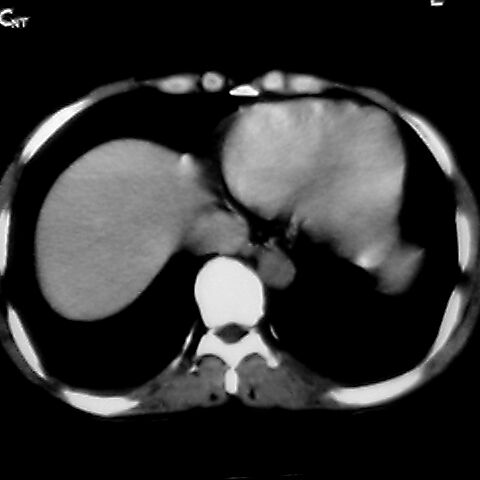

女 48岁 食道癌术前体检发现脾占位。

脾胀内部巨大低密度肿块,边界清或不清,中心坏死,轻度增强,内见散在钙化,结合食道癌病史多考虑:转移癌.

脾脏低密度灶伴钙化,增强化明显,中心见液化坏死灶,强化延时明显。考虑血管瘤。转移瘤待排。

右肾见类圆形低密度影.结合病史.脾及右肾转移性ca可能性大